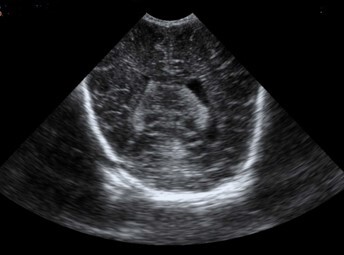

Neonatology Choroid Plexus 2 Image